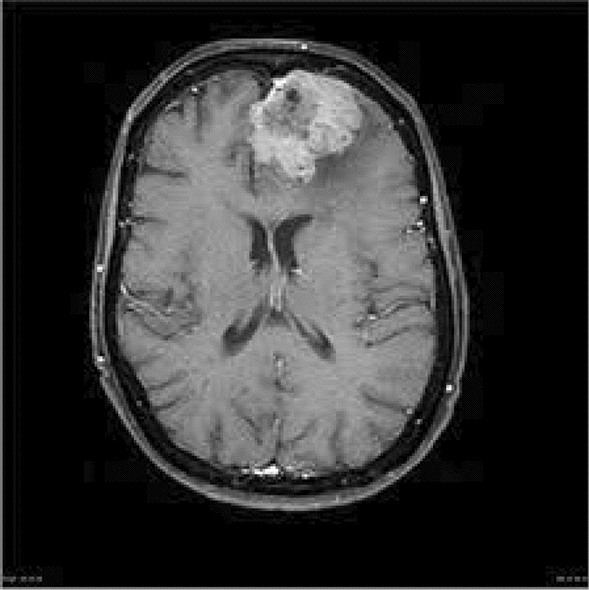

Brain Tumor Detection

An AI model designed to detect brain tumors from MRI scans.